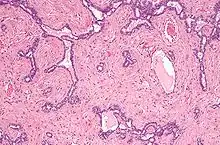

Vertical section of the testis, to show the arrangement of the ducts. Micrograph of the rete testis involved by seminoma. H&E stain.

Micrograph of the rete testis involved by seminoma. H&E stain. Tubular ectasia of the rete testis